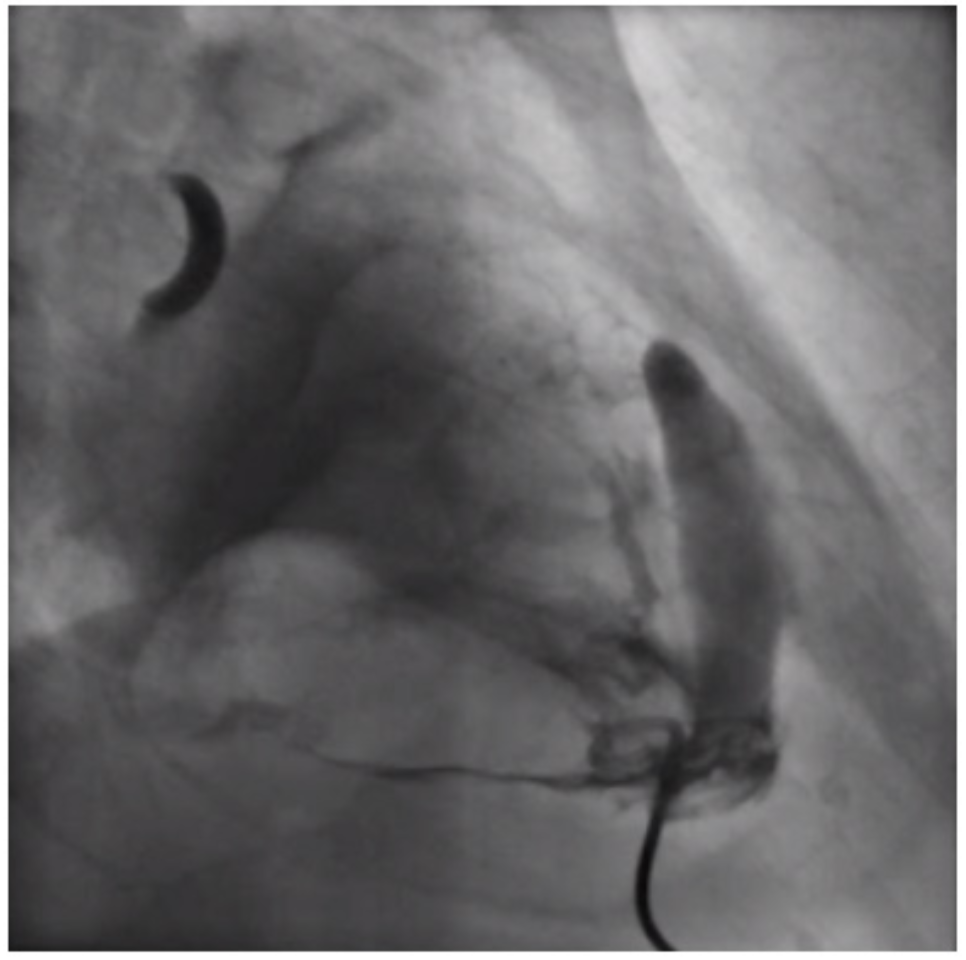

Fluid replacement and vasopressor were initiated as blood pressure began to drop. Orotracheal intubation was performed due to respiratory failure. The patient was transferred to the catheterization laboratory for emergency cardiac catheterization. Coronary angiography showed a thrombotic occlusion of the distal left circumflex artery (LCX) and proximal marginal branch. The proximal left anterior descending artery (LAD) and right coronary artery (RCA) had severe lesions (Figure 1). Due to hemodynamic deterioration, pericardiocentesis was performed with a pigtail catheter (Figure 2) with transient improvement, but failed to empty the pericardium due to continuous blood filling. Hemodynamics continued to deteriorate and several cardiac arrests developed, with transient returns of spontaneous circulation. After considering the condition irreversible, we injected contrast in the pericardium to confirm diagnosis, showing 2 perforations in the left ventricular free wall (Video 1). The patients died minutes later.